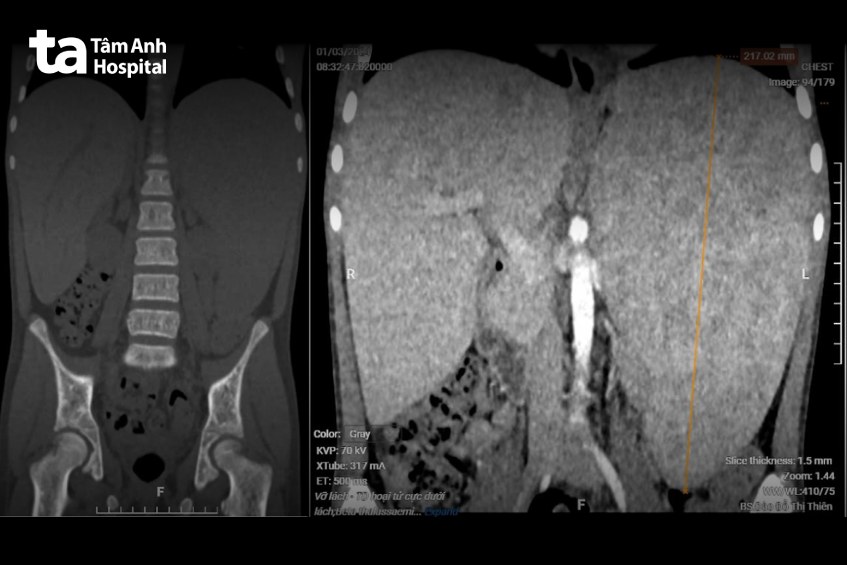

Ngày 2/1, Tiến sĩ bác sĩ Phạm Công Khánh, Trưởng khoa Gan – Mật – Tụy, Trung tâm Nội soi và Phẫu thuật Nội soi Tiêu hóa, Bệnh viện Đa khoa Tâm Anh TP HCM cho biết kết quả chụp cắt lớp vi tính (CT) cho thấy lách người bệnh to độ 4 (mức độ cao nhất), với chiều cao của lách là hơn 21 cm (bình thường khoảng 7-14 cm). Vùng dưới lách còn có mảng tổn thương kích thước dài gần 5 cm, nghi ngờ nhồi máu lách.

“Lách to là diễn biến thường gặp của người mắc bệnh thiếu máu bẩm sinh (bệnh beta thalassaemia)”, bác sĩ Khánh cho biết, thêm rằng lách càng to người bệnh phải truyền máu càng nhiều. Nguy cơ cao xảy ra biến chứng như nhồi máu lách, vỡ lách gây chảy máu ổ bụng, đe dọa tính mạng. Cắt lách là chỉ định cần thiết để giảm nhu cầu truyền máu cho bệnh nhân, đồng thời phòng ngừa biến chứng nguy hiểm.